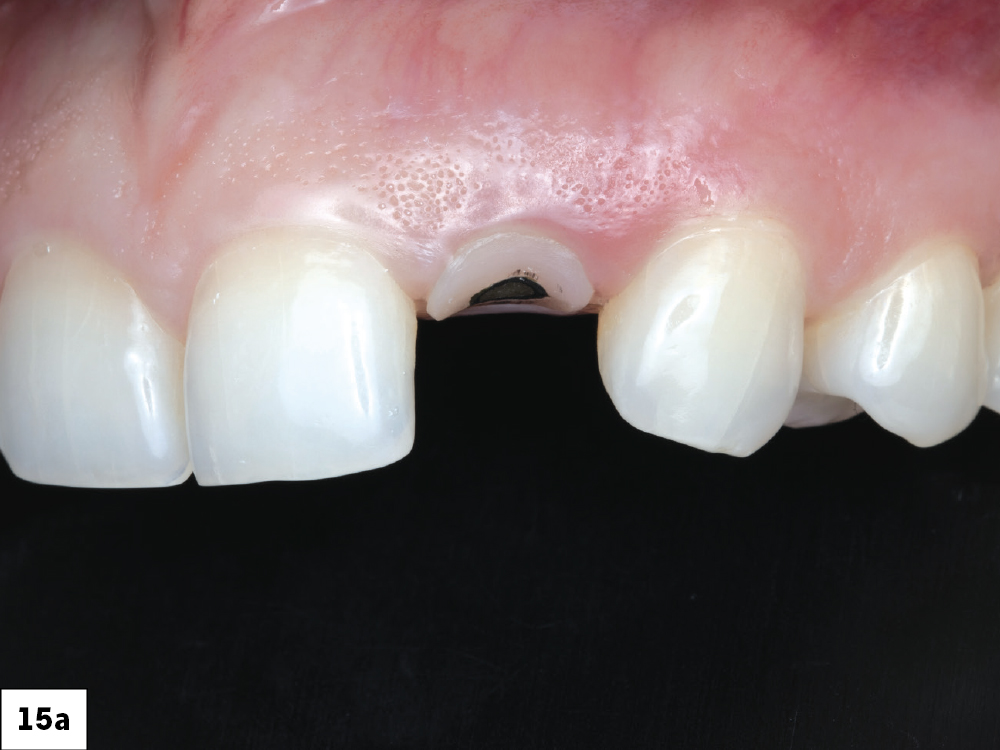

The patient returned three months later for an evaluation. The gingival architecture was observed to be well-maintained and healed effectively. A shade map of the tooth was created and documented.

Figures 15a, 15b: The patient returned three months later for an evaluation. The gingival architecture was observed to be well-maintained and healed effectively. A shade map of the tooth was created and documented.